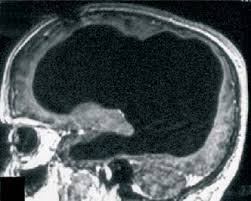

Bărbatul a mers la medic invocând faptul că resimte o oarecare slăbiciune în piciorul stâng. Supus la o ecografie generală, medicii au fost uimiți să descopere faptul că cea mai mare parte din creierul bărbatului era umplută cu lichid, având doar un strat subţire de ţesut cerebral, părţile interne fiind erodate aproape în întregime.

Medicii cred că cea mai mare parte a creierului a fost distrus în timp, printr-un proces extrem de lent și insesizabil, cauzat de o afecțiune cunoscută sub numele de hidrocefalie. Acesta fusese diagnosticat cu această boală din copilărie şi a fost tratat cu un stent, însă la vârsta de 14 ani acesta a fost îndepărtat. De atunci, cea mai mare parte a creierului său a fost erodat.